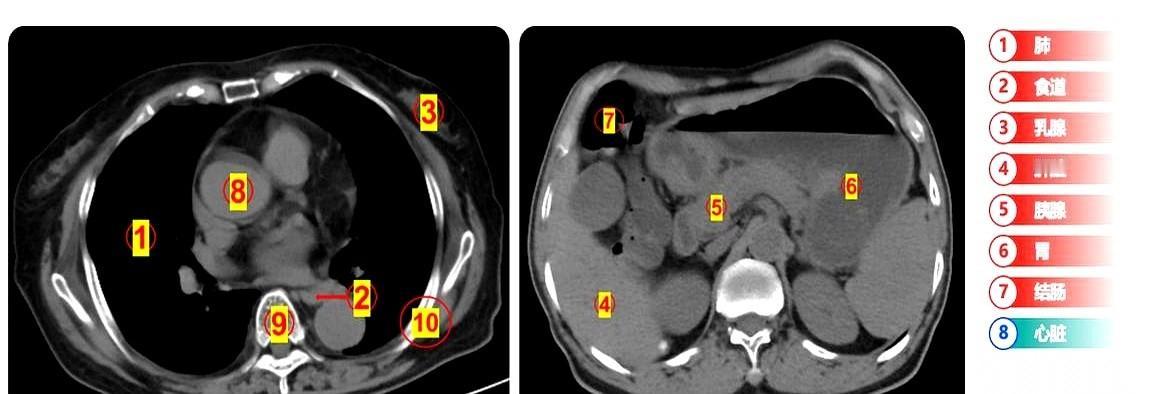

GE,那个卖CT机卖了一百年的美国老祖宗,居然反过来找阿里达摩院“拜码头”了。 就为了一个AI技术。 这事儿,比小说还精彩。 你以为放射科医生是神仙?天天对着成千上万张黑白片子,眼都快看瞎了,还生怕看漏了哪个小点点,那背后可是一条命。 现在,阿里搞了个“一扫多查”。 病人躺进去,CT机“嗡”一圈,AI就把你肺里的结节、肝上的囊肿、骨头里的小毛病……一次性全给你揪出来,标得清清楚楚。 效率翻几倍都是小事,关键是它把医生从快要淹死的报告堆里捞了出来。 你说,这玩意儿香不香? GE当然懂。它家的机器是牛,是全球顶配,但现在这年头,光有个强壮的身体没用了,你得有个聪明的大脑啊。 再不给自己装个“中国脑”,旁边虎视眈眈的西门子、飞利浦,还有中国本土那些“自带AI基因”的狠角色,分分钟就能把它挤到墙角去。 这不是面子问题,是生死问题。华尔街那帮人可不听你讲情怀,他们只看报表。 所以你看,这事儿多有意思。 老美天天琢磨着怎么在硬件上卡我们脖子,不卖芯片,搞技术封锁。 他们以为锁住了“身体”,我们就动弹不得了。 结果呢? 我们直接换赛道,开始输出“灵魂”了。 我的算法,装进你的机器,你的机器才能卖得更好。我的“大脑”,决定了你“身体”的价值。 这叫什么? 这就叫,你堵你的阳关道,我走我的独木桥,走着走着,我的独木桥,变成了通天大道。 一个代码和数据组成的AI,你怎么封锁?靠网线吗? 时代真的变了。 以前是“美国创新,中国组装”,现在,轮到我们的智慧,去定义全世界的下一代产品了。 这感觉,真带劲。